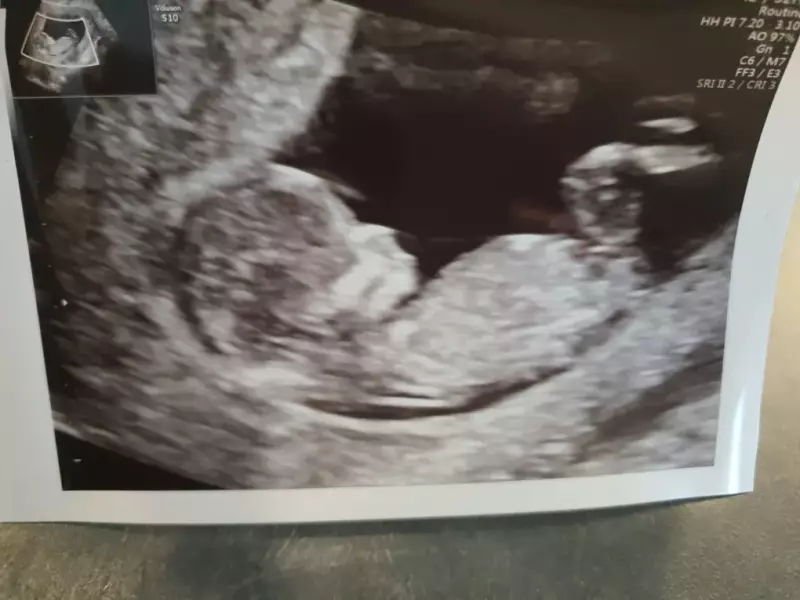

Toinen juttu on ollut melkoisen paha väsymys ja pahoinvointi tässä kesän aikana. Johtuen siitä, että masussa kutittelee Kallionklaanin uusin jäsen, joka liittyy meidän joukkoon todennäkösesti helmikuun lopulla eli nyt mennään viikolla 16+1 ja laskettuaika on 29.2. Isosiskot odottaa jo niin super innoissaan uutta pikkusisarusta, että masu saa pusuja ja haleja päivittäin kymmeniä!

Meillä on alkanut firman asiat pyöriä onneksi hienosti ja nyt kun omakin olo alkaa viimein tuntua taas paremmalta, pystyn keskittyyn taas erilailla tähän kirjoittamiseenkin. Masu alkaa jo kivasti pyöristyä ja tosiaan liikkeet on tuntunut tästä kolmannesta nyt tosi aikaisin, jo viikolla 12+ tuntui ensimmäiä sipaisuja ja pieniä potkuja. Esikoisesta tunsin liikeet viikolla 17+ ja kuopuksesta viikolla 14+. Tää aika on vaan joka kerta yhtä ihanaa ja ainutlaatusta. Tietty sen verran alussa vielä ollaan, ettei liikkeet ole kovinkaan selviä vielä ja joutuu paljon kuulostelemaan tuntemuksia, minkä takia välillä on mielessä käynyt pelko siitä, että onhan kaikki varmasti masussa hyvin. Dopplerilla oon saanut onneksi varmistusta omaan panikointiin kivasti ihan kotioloissa! Oma panikointi varmasti juontaa juurensa keväällä 22 saamaani keskenmenoon, mutta onneksi nyt kaikki on mennyt hyvin <3